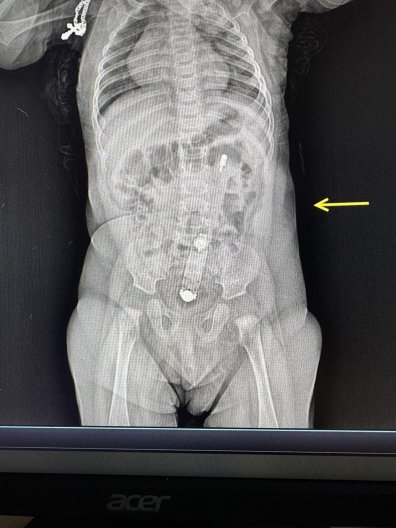

В Волынской области в больнице поступил полугодовалый ребенок, в толстом кишечнике которого застрял электронный термометр. Как оказалось, у девочки был запор, а ее мать хотела помочь.

На рентгене был отчетливо виден термометр. Его также можно было прощупать пальцами через живот. По словам хирурга и эндоскописта Юлии Артишук, достать прибор было довольно непросто.

"Сделали это эндоскопически. Действовать нужно было очень осторожно, чтобы не травмировать младенцу анус и внутренние органы. Самостоятельно градусник выйти не мог, вместо этого мог перфорировать кишечник или в дальнейшем спровоцировать кишечную непроходимость", — объяснила она.